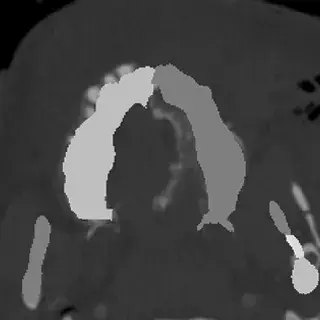

3D Systems' VSP® surgical planning solutions for craniomaxillofacial (CMF) applications received FDA clearance as a service-based approach to personalized surgery over 10 years ago.

3D Systems and Stryker Corporation have partnered to provide surgeons with best-in-class products and services for craniomaxillofacial surgeries. As a leader in personalized healthcare solutions, 3D Systems has planned and delivered devices for more than 140,000 patient-specific cases. The Stryker Craniomaxillofacial business specializes in providing patient-specific options and innovative solutions that help drive efficiencies in surgical suites. The combination of Stryker’s specialized team and advanced implants with 3D Systems' cutting-edge 3D printing technologies and expert consulting services positions both companies to provide a superior level of service to healthcare professionals who use these revolutionary solutions.